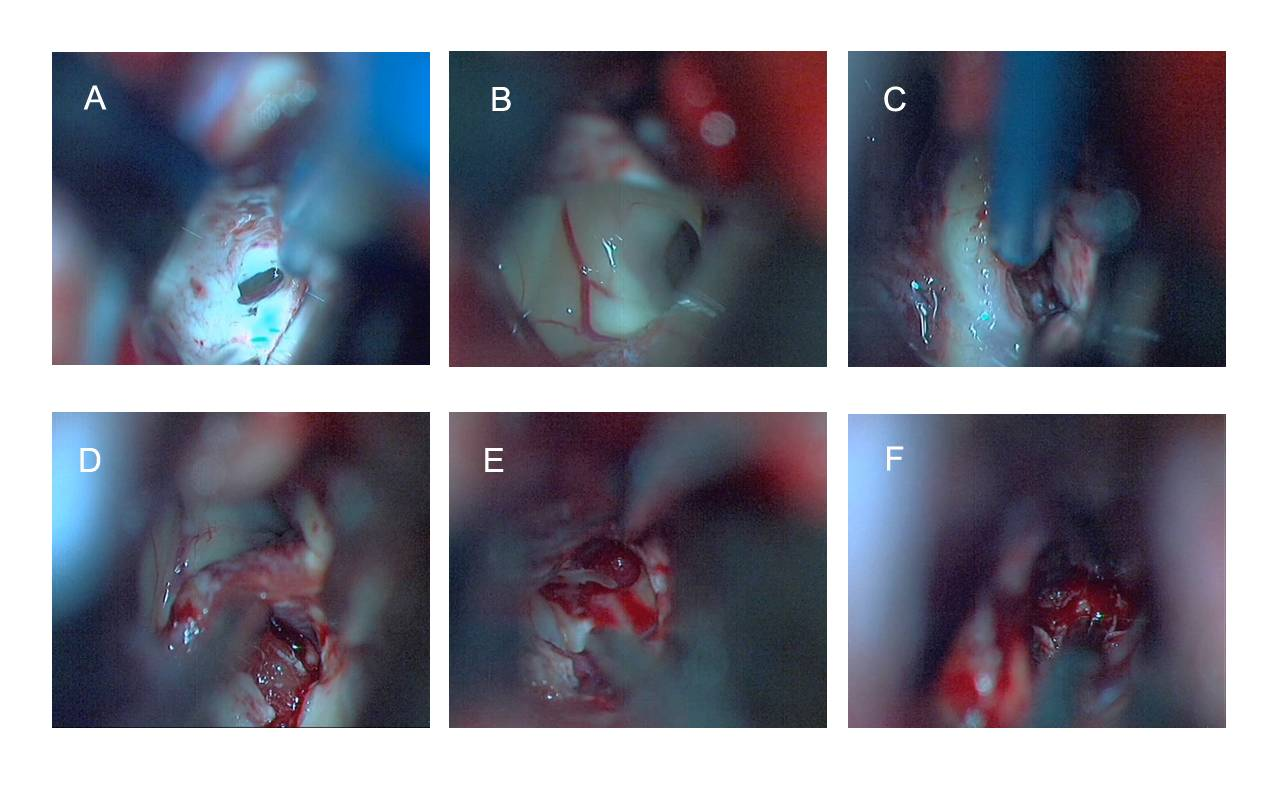

考虑肿瘤位于鞍上突入三脑室为主,行全麻下发际内冠状缝前右额小骨窗开颅,经胼胝体入路肿瘤切除术。术中见肿瘤呈灰红色,血供非常丰富,质地较韧,切除困难(图4)。取部分标本送冰冻检查,结果提示:见增生胶质样细胞并散在细胞核较大、核仁明显,不除外节细胞胶质瘤可能。

图4. A:显示沿大脑镰牵拉开额叶,暴露胼胝体,沿中线切开胼胝体,可见侧脑室;B:经侧脑室可见左侧室间孔;C:在侧脑室脉络丛内侧,经透明隔-穹窿间进入三脑室内;D:探及三脑室内肿瘤;E和F:可见肿瘤血供较丰富,质地偏韧,行部分切除肿瘤。